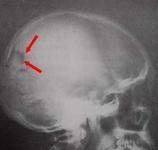

顱骨結核是因全身各部位的活動性結核病灶的結核桿菌侵入顱骨而引起的一種特異性炎癥反應,致使顱骨破壞并向周圍組織蔓延,炎癥的擴散因骨縫的限制,一般不超出該塊顱骨范圍,如治療不及時可引起一系列嚴重的并發癥,造成不良后果。